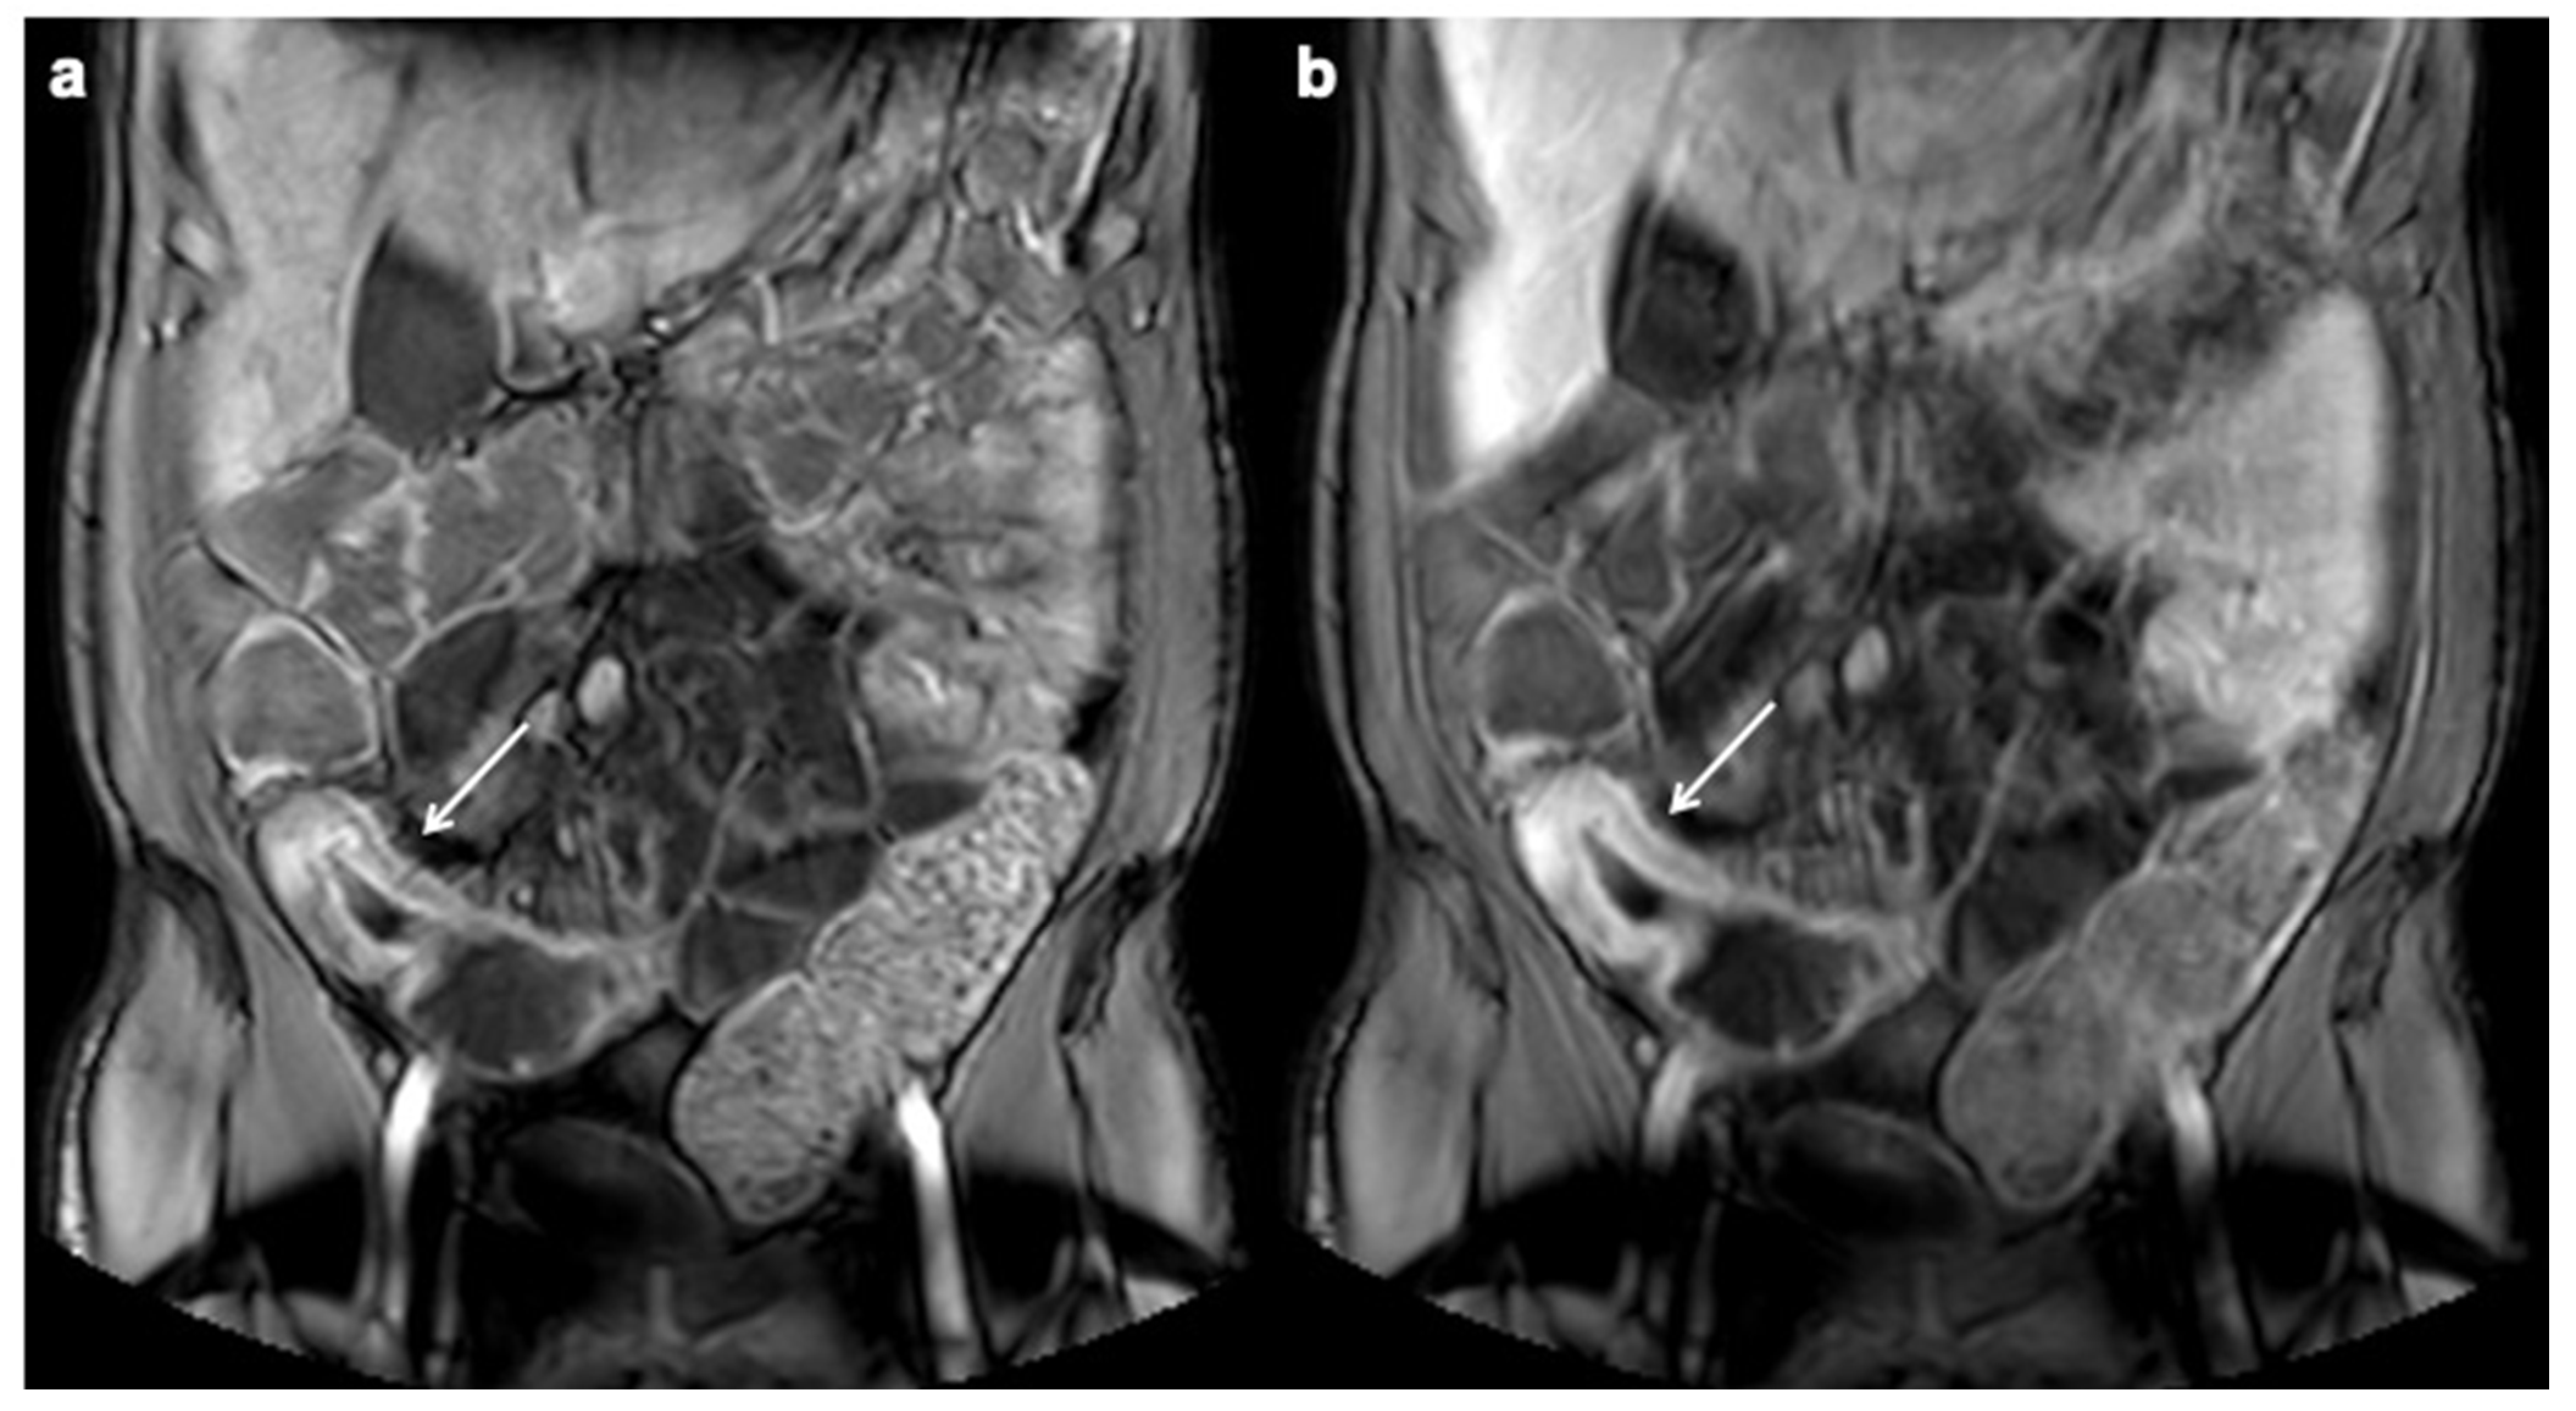

- Church, P.C.; Turner, D.; Feldman, B.M.; Walters, T.D.; Greer, M.-L.; Amitai, M.M.; Griffiths, A.M.; the ImageKids study group. Systematic review with meta-analysis: Magnetic resonance enterography signs for the detection of inflammation and intestinal damage in Crohn’s disease. Aliment. Pharmacol. Ther. 2014, 41, 153–166. [Google Scholar] [CrossRef]

- Tolan, D.J.M.; Greenhalgh, R.; Zealley, I.A.; Halligan, S.; Taylor, S.A. MR Enterographic Manifestations of Small Bowel Crohn Disease. RadioGraphics 2010, 30, 367–384. [Google Scholar] [CrossRef] [Green Version]

- Sinha, R.; Verma, R.; Verma, S.; Rajesh, A. MR Enterography of Crohn Disease: Part 2, Imaging and Pathologic Findings. Am. J. Roentgenol. 2011, 197, 80–85. [Google Scholar] [CrossRef] [Green Version]

- Rimola, J.; Rodriguez, S.; Garcia-Bosch, O.; Ordas, I.; Ayala, E.; Aceituno, M.; Pellise, M.; Ayuso, C.; Ricart, E.; Donoso, L.; et al. Magnetic resonance for assessment of disease activity and severity in ileocolonic Crohn’s disease. Gut 2009, 58, 1113–1120. [Google Scholar] [CrossRef] [PubMed] [Green Version]